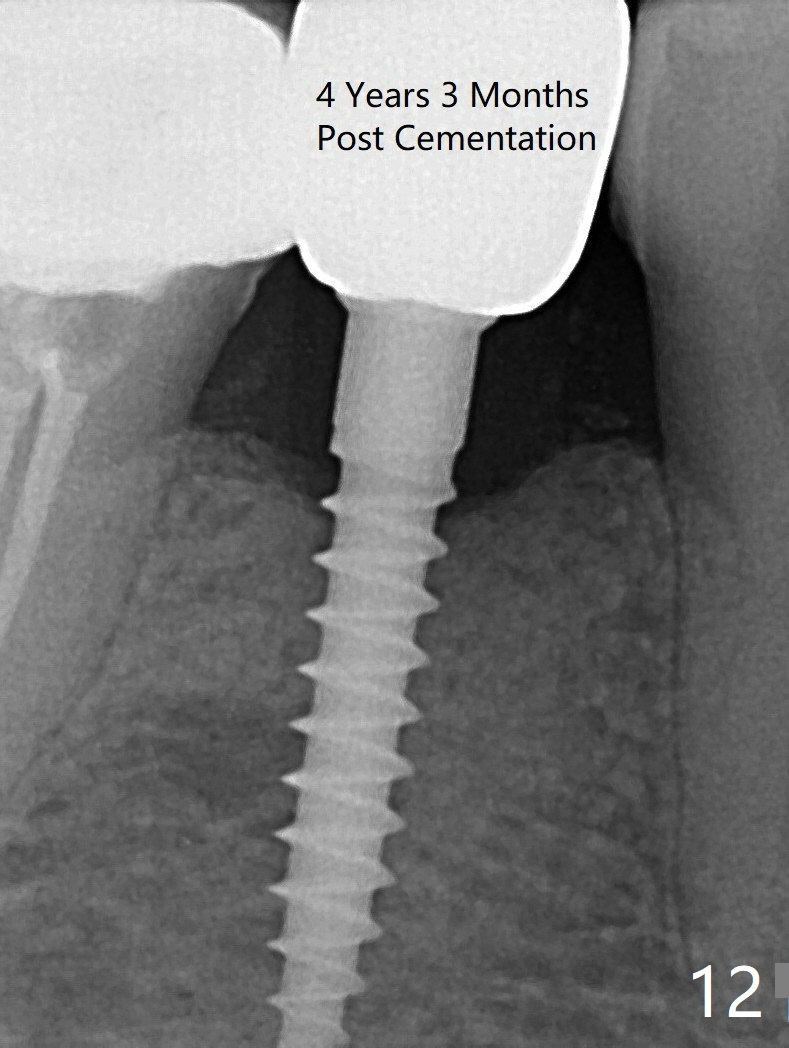

Preop photo shows the distal inclination of the tooth #28 (Fig.1). The distal surface of the latter is reduced before incision for implant placement at #29 (Fig.2). The buccolingual width is approximately 4 mm, as compared to 3 mm implant positioner (Fig.3). After 1.2x10 mm osteotomy (Fig.5), the mesiodistal cortical bone is removed with a small high-speed fissural bur (Fig.4). When a 2.5x12(2) mm 1-piece implant is placed (Fig.6), there is no buccal (Fig.7) or lingual plate perforation. There is no postop paresthesia. There is mild bone loss distal 4 months postop (Fig.8 *). Take photos before and after permanent crown cementation to show increase in ridge width after bone graft and improvement in gingival health after provisional modification. Take PA and/or BW post cementation to show that the distal bone resorption (Fig.8 *) is partially due to angulation. No continuous bone loss 15 months post cementation (Fig.9). There is mild bone resorption mesially 2 years 3 months post cementation (Fig.10). The soft and hard tissues remain healthy 4 years 3 months post cementation (Fig.11,12).